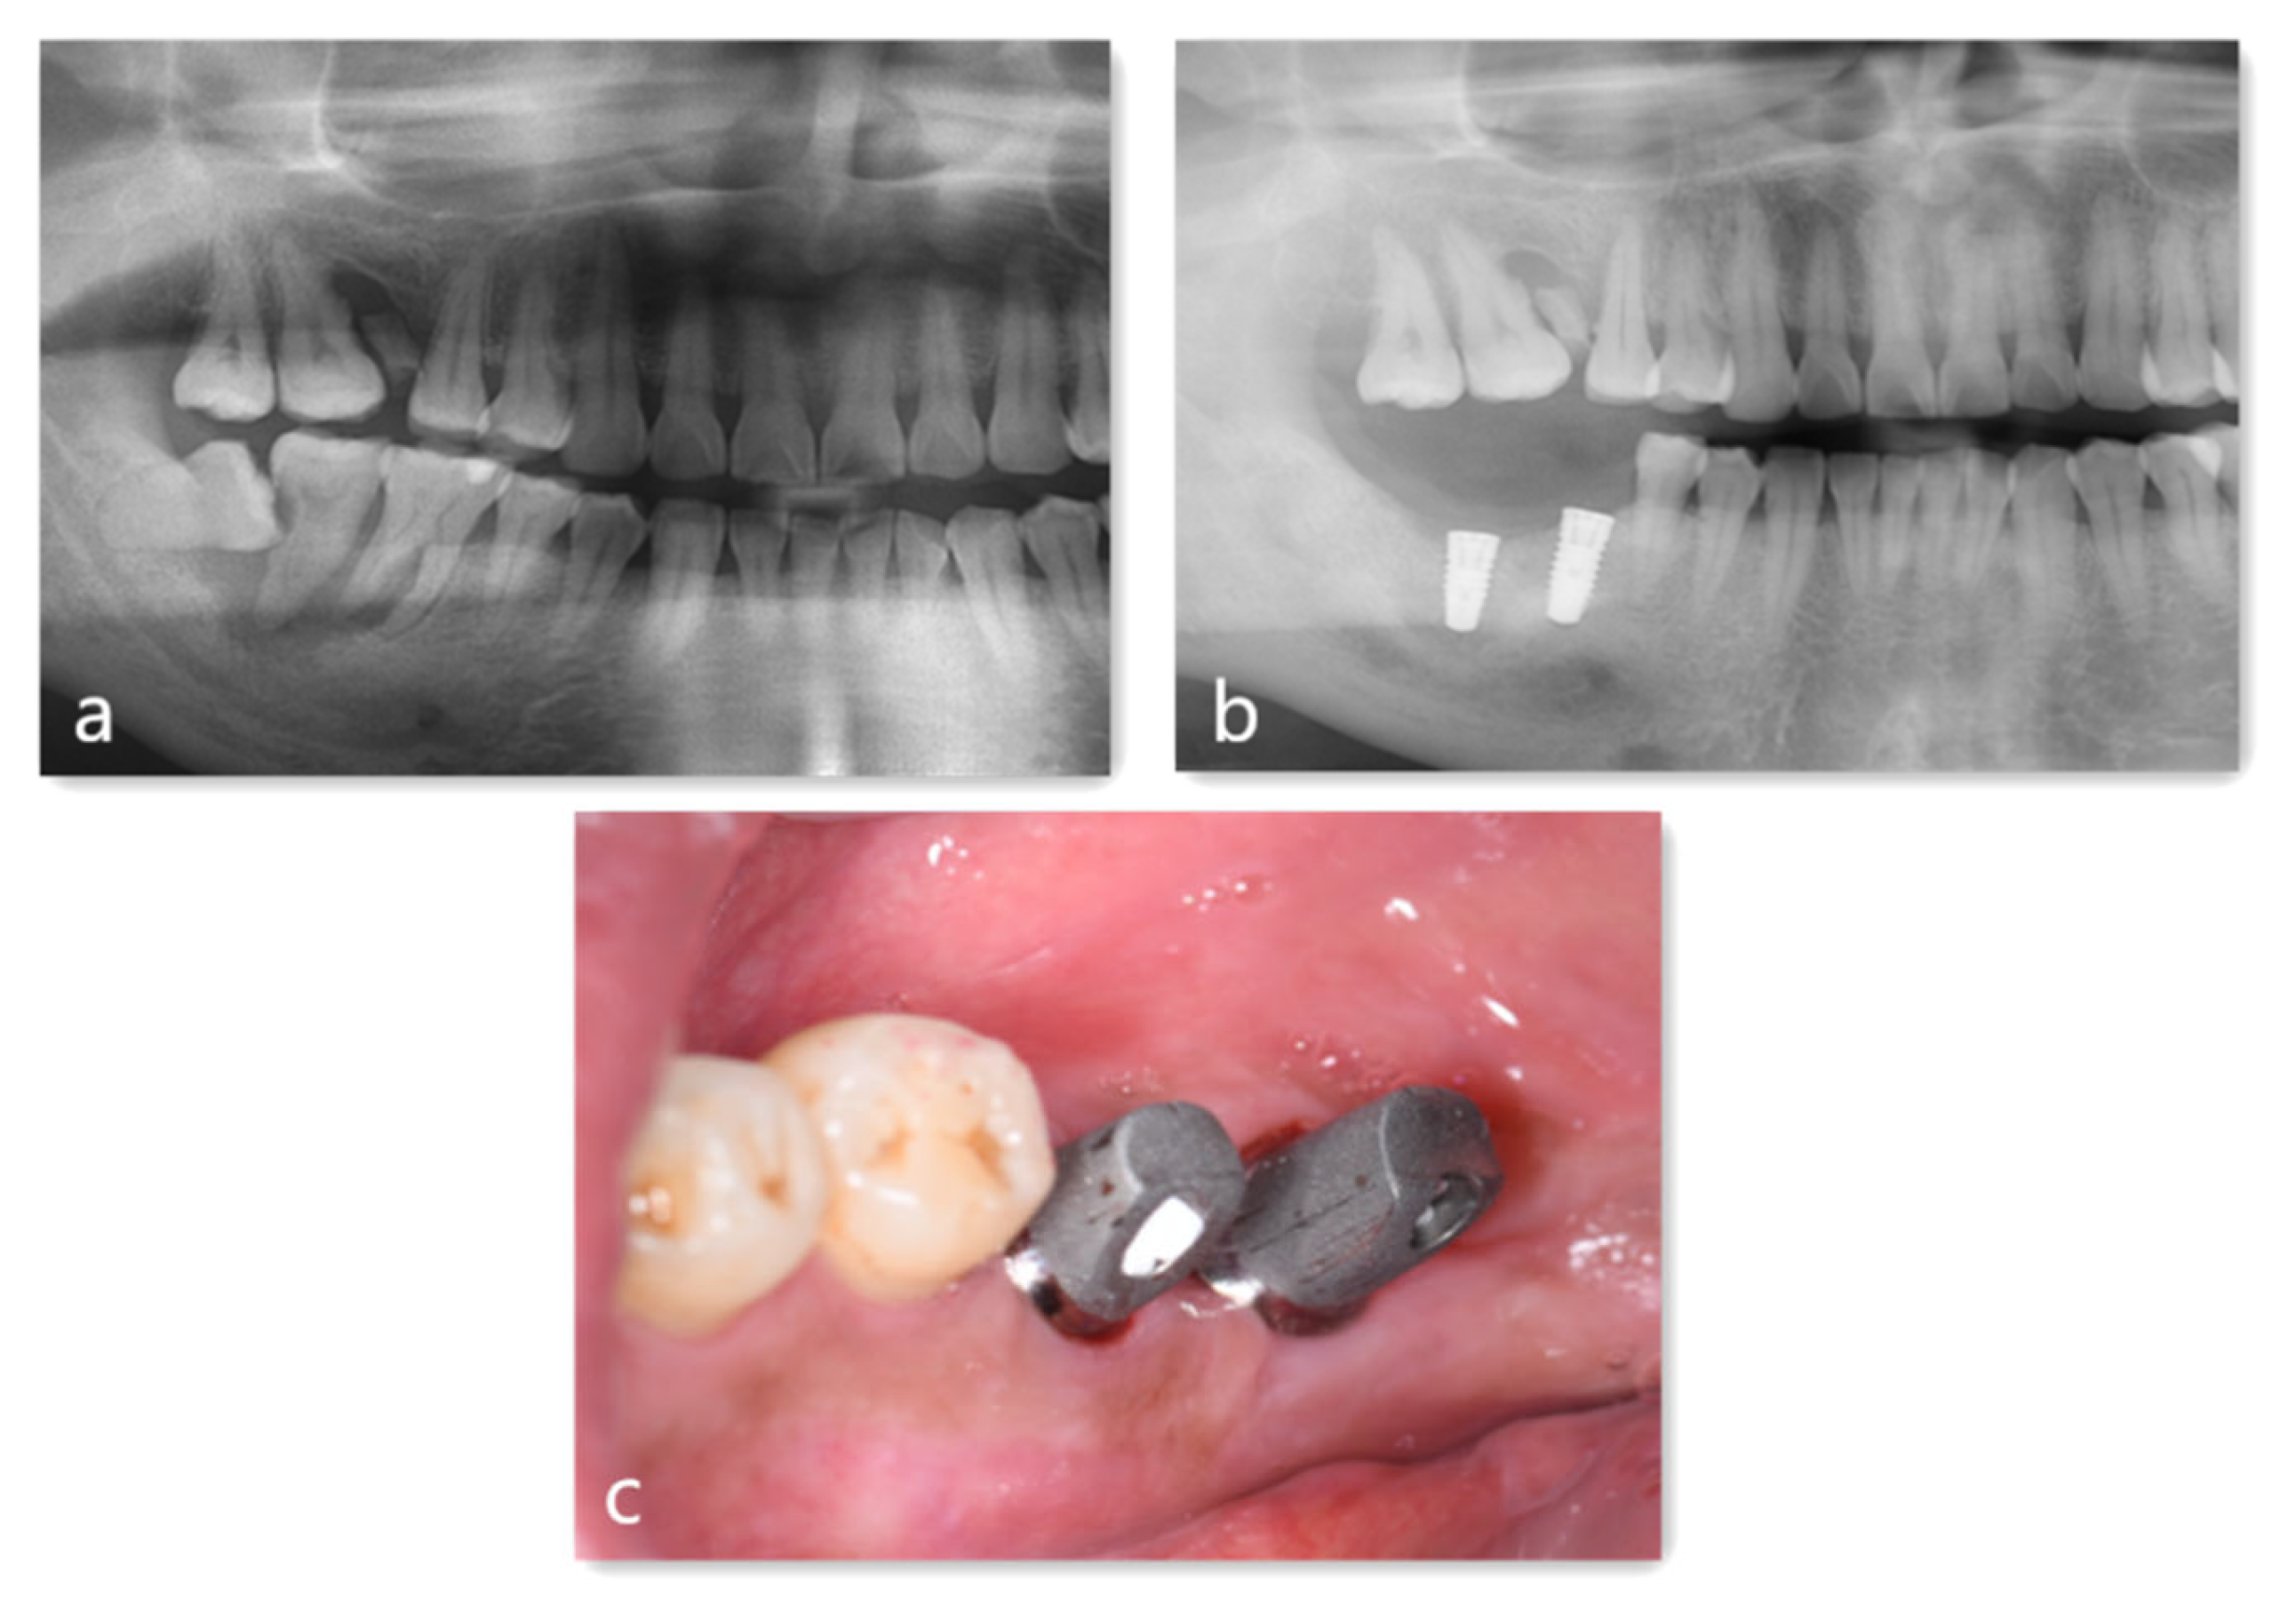

4. Case Report